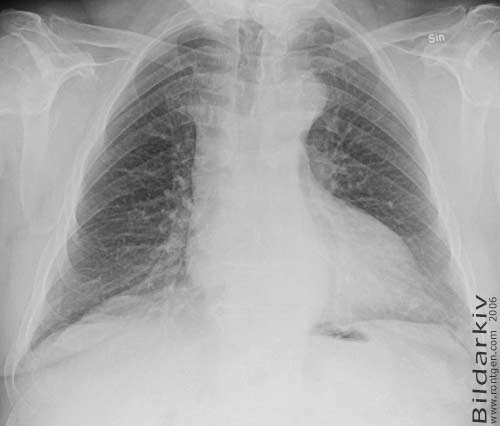

18a Lungorna kvinna 52 år

Frontal bild av lungorna på 52 årig kvinna.